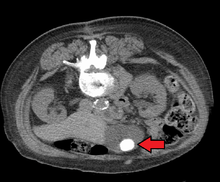

Images of a CT of gallstones